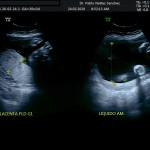

- El escenario Gravídico: Placenta, liquido y Anexos.